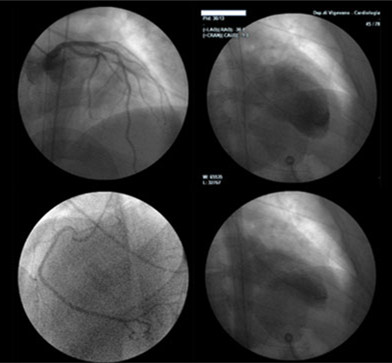

TCM的实际发生率尚不清楚,但该病可能占所有疑似急性心肌梗死病例的1%~2%。TCM患者一般表现为胸痛、心电图ST段抬高和心肌酶水平升高,与急性MI的表现是一致的。但当患者行冠状动脉血管造影术时,可发现无显著冠状动脉狭窄(如图所示),而左心室造影显示左心室心尖部存在球样扩张。

左图:服用多种药物自杀因药物毒性引发TCM的患者,冠脉血管造影正常。

右图:该患者的舒张期(上图)和收缩期(下图)左室血管造影显示心尖部运动减少。